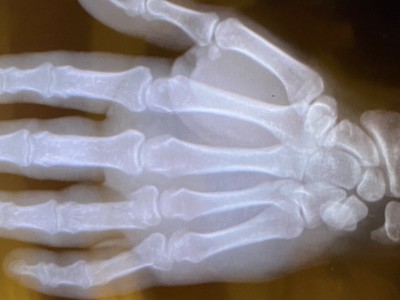

491Zet'm op! Alle tijd nu voor reflectie, als je dat al niet deed. Beterschap!

Sterkte Frans.

, eerst Cremalover, nu Frans G ( als de hevel nog maar bediend kan worden)